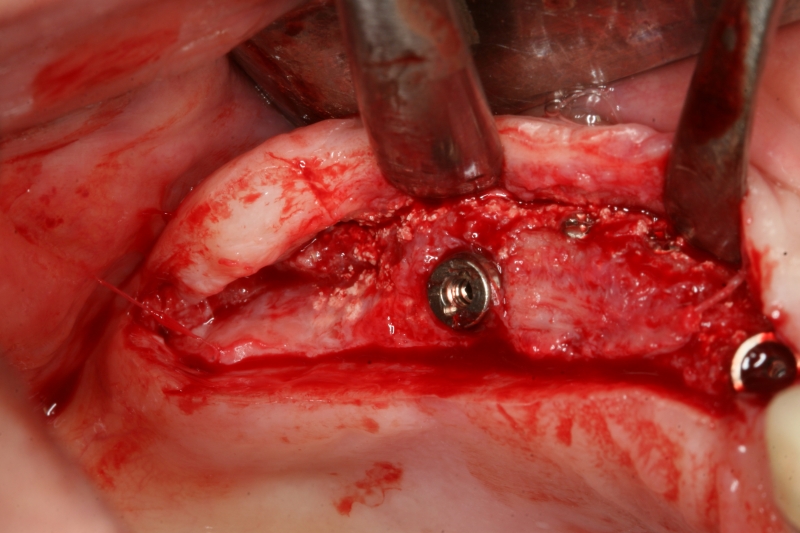

Implant insertion in atrophic alveolar ridge